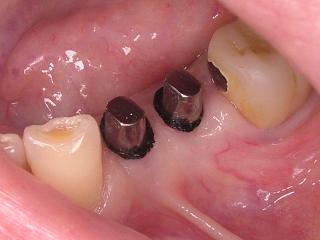

形成ではなくインプラントの症例ですが考え方は一緒です。

歯ぐきのラインより下まで型がとれているのがお分かりいただけると思います。